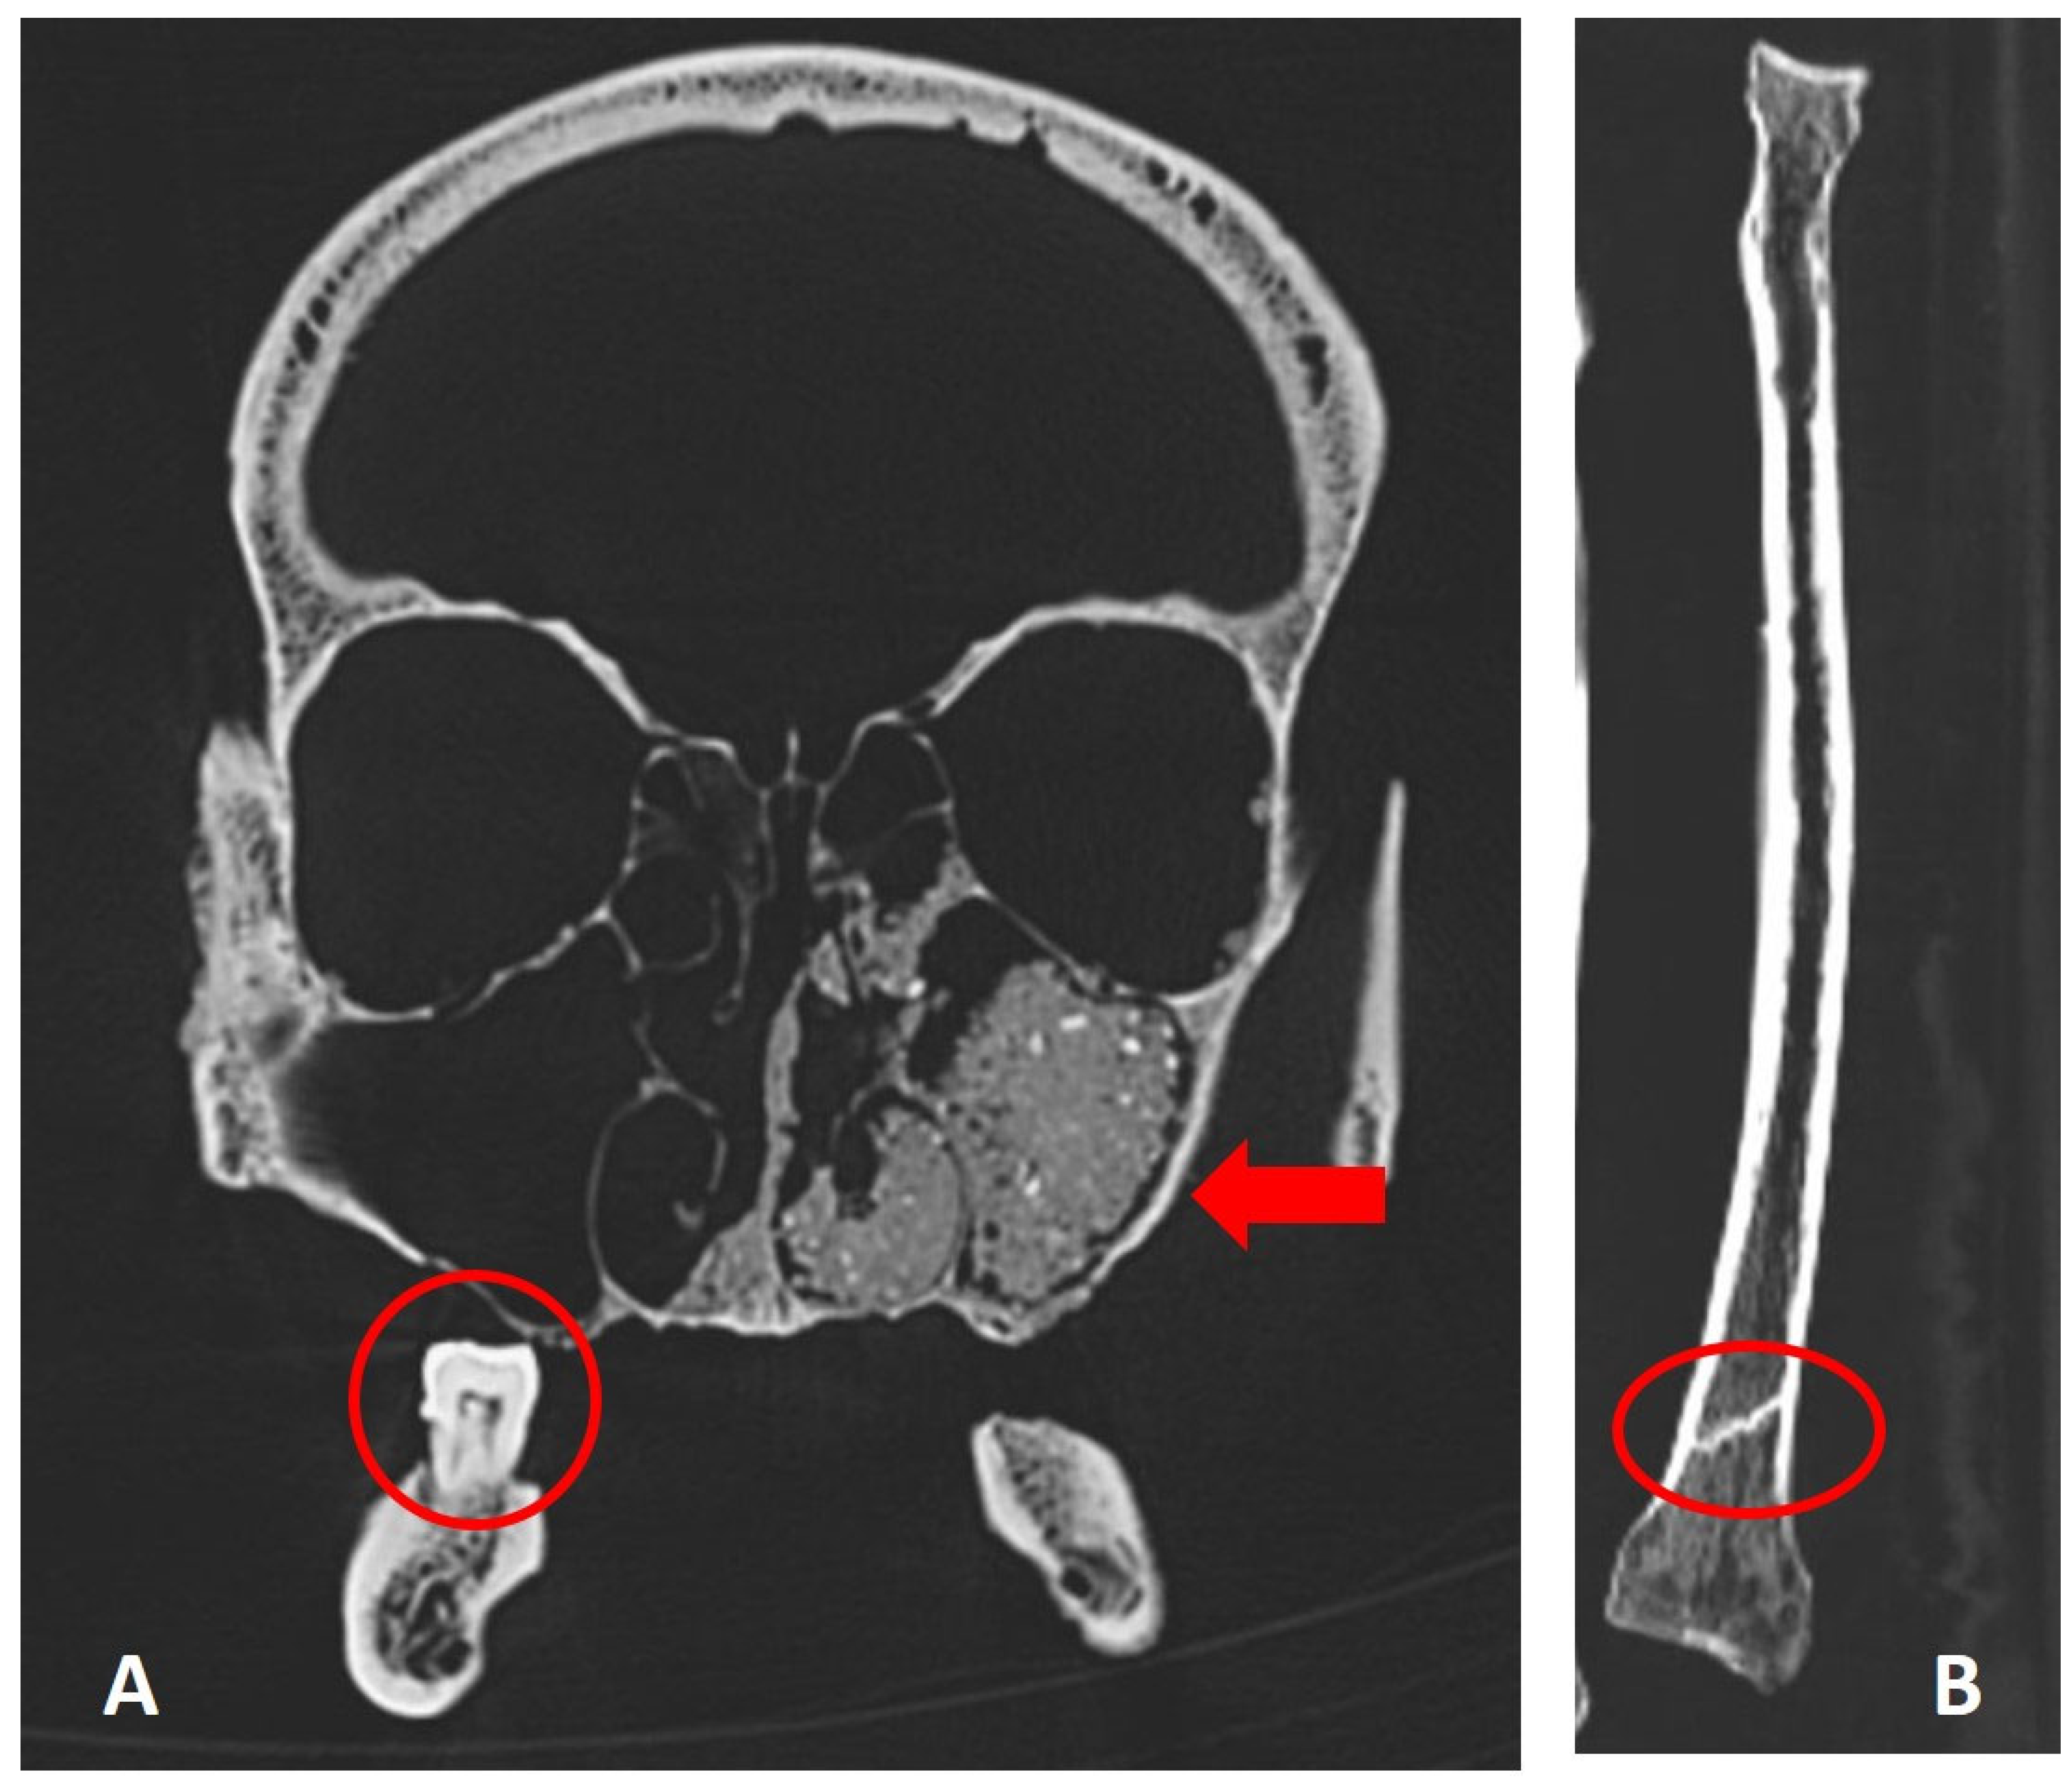

The scanning of all available bones confirmed the macroscopic observations. All preserved vertebral bodies and the fragments of both hemipelvises showed widespread mixed osteolytic-osteoblastic bone defects highly suggestive of multiple osseous metastases (Figure 8A, B). Additionally, isolated, mostly osteolytic lesions were seen in the skull, mainly lacking the osteoblastic component (Figure 8C). In addition, the CT scans showed additional metastatic infiltration in the left temporo-mandibular joint which was macroscopically unremarkable (Figure 8D). In contrast, long bones and the few small bones of the feet remain free of abnormal lesions. In general, the mineralisation of the skeleton was fairly well preserved with no signs of significant generalised osteopenia.

In the jaws, the CT scans also confirmed the presence of old-healed tooth loss in the whole maxilla, and several “younger” tooth losses in the central mandible with still partly preserved dental alveoli. Only the tooth of region 47 was present (Figure 9A). In the paranasal sinuses, the scans show almost complete filling by external soil material (Figure 9A). Finally, the distal right radius shows an oblique bone bar in the distal metaphysis (Figure 9C).

Figure 9. Further CT-scan features: A) Coronal reconstruction through the skull showing soil in the paranasal sinuses (arrow). Note the single preserved tooth in region 47 (circle). B) Coronal reconstruction of the right radius showing an oblique bone bar in the distal radial metaphysis (circle) (images: S. Panzer).